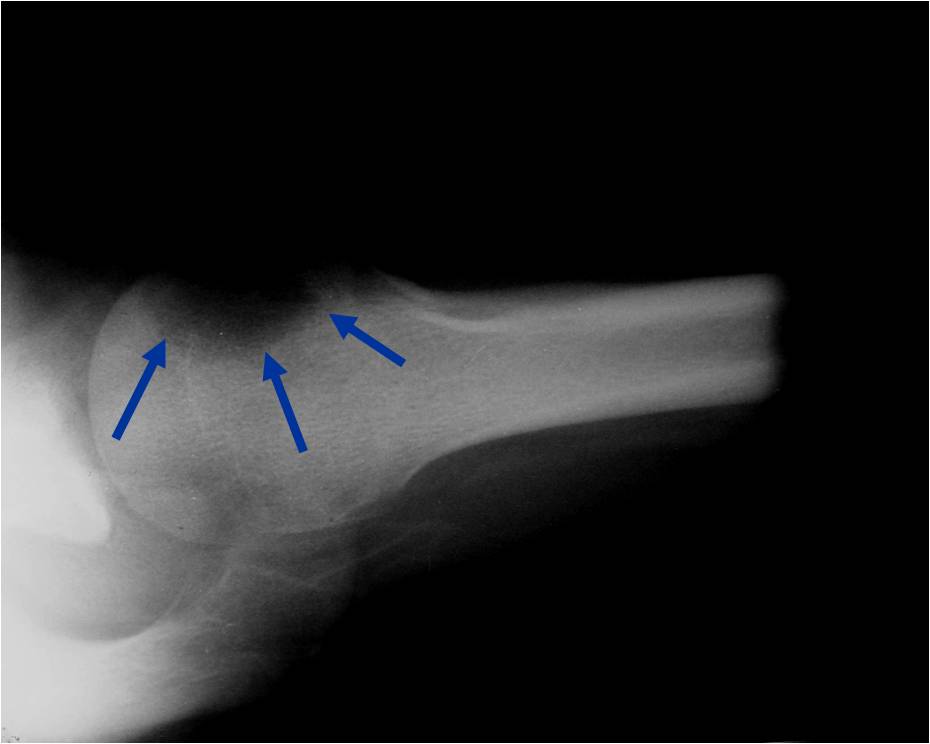

Radiographic Presentation

- Presents as a highly defined/well circumscribed geographic oval/round lytic defect

- Surrounded by rim of sclerotic bone

- Usually in epiphyseal region

- Lesion ranges from 3 cm to 6 cm diameter

- Usually radiolucent

- May have fine trabeculae and irregular calcifications

- Calcifications are often better detected with a CT scan but are not uniformly present

- Lesions may expand the bone and new periosteal bone may form

- Bony end plate, cortex, bone contour are unaffected

Plain x-ray appearance:

- Geographic lytic lesion IA/IB margin of sclerosis

- Usually Eccentric more often than Central in the bone

- Rarely expansile (rarely penetrates the cortex)

- Calcified chondroid matrix 30%-50% of cases

- Often better detected with a CT Scan

- Periosteal Reaction 30-50% of cases

- Usually occurs in Adjacent Diaphysis/Metaphysis since epiphysis is intraarticular and not surrounded by periosteum